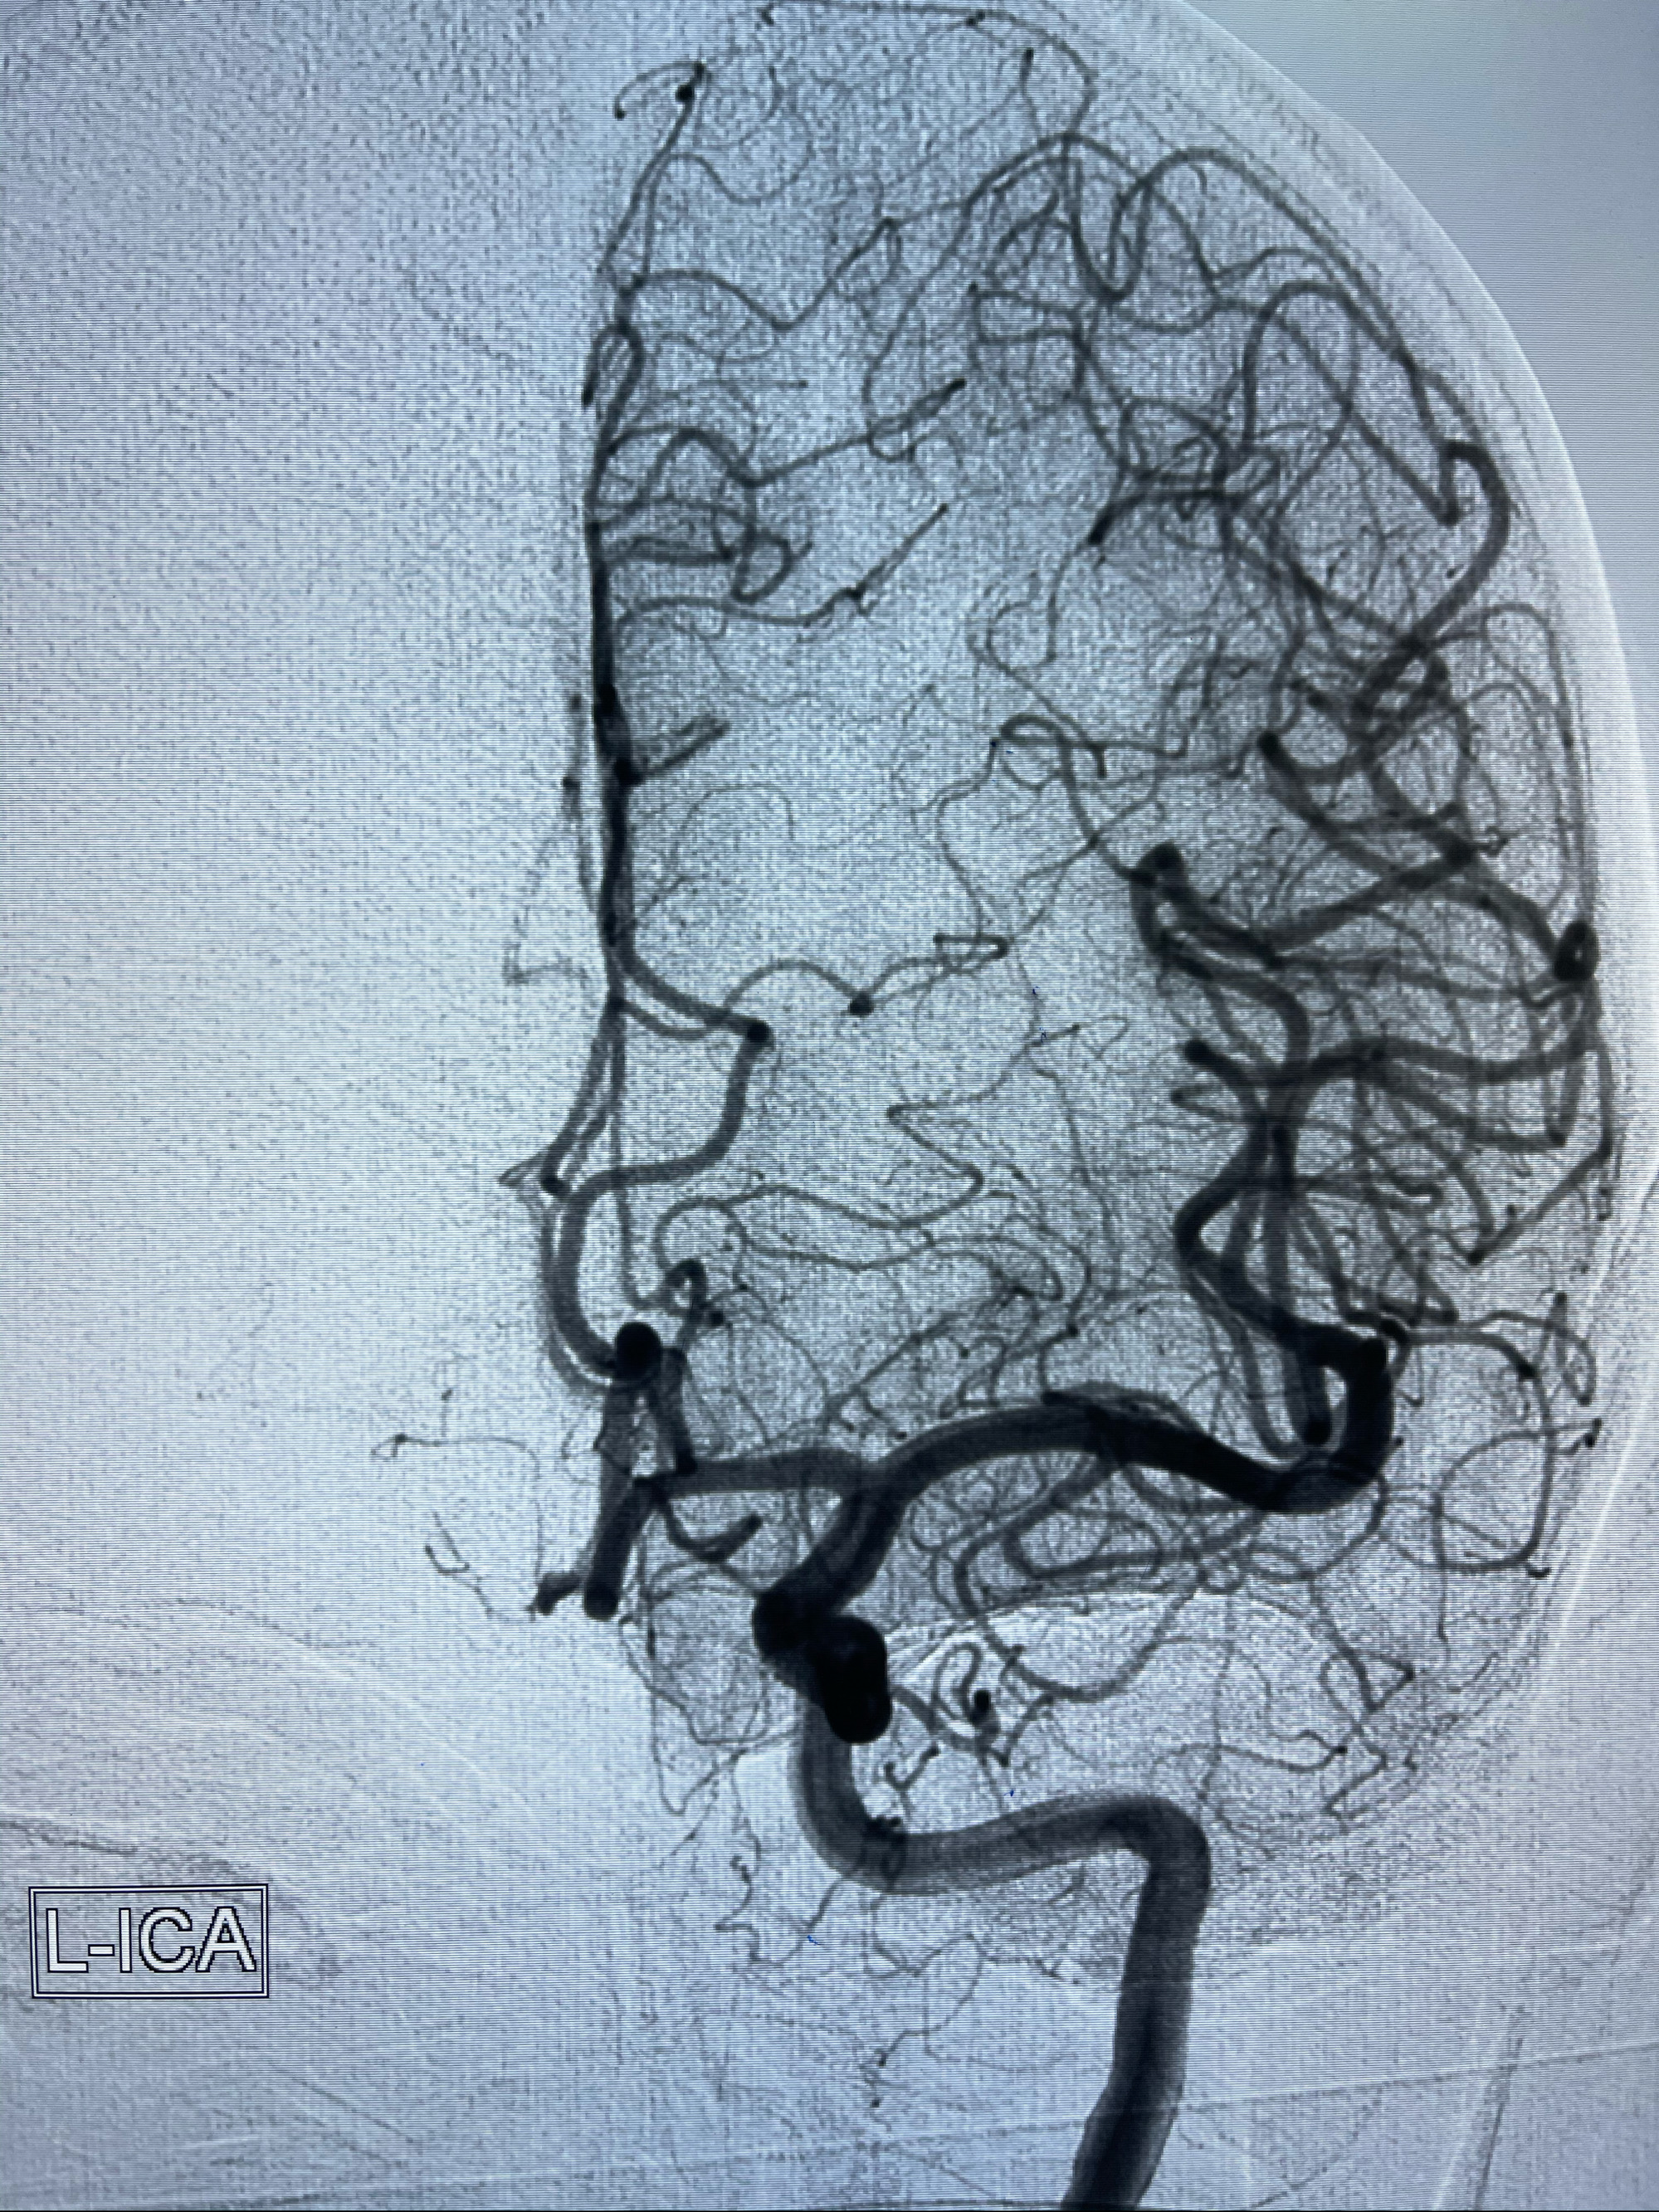

2021-03-08行全脑血管造影

1.右侧颈内动脉夹层动脉瘤Lvis支架辅助;

右侧颈内动脉夹层动脉瘤Lvis5.5-20mm支架辅助栓塞